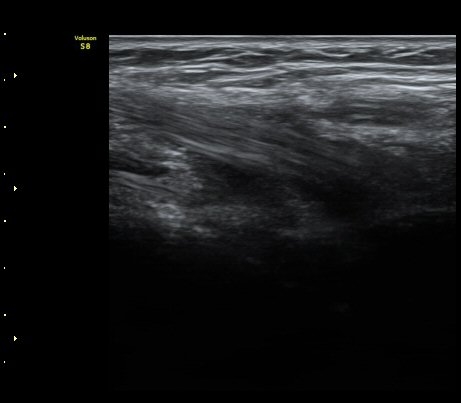

ÆÈ²ÞÄ¡ ¾Õ Ⱦ´Ü¸é°Ë»ç¿¡¼­ À̵ιڱÙÀÌ ÈûÁÙ·Î ÀÌÇàµÇ´Â °ÍÀÌ °üÂûµÈ´Ù(±×¸² 1, 2).

ŽÃËÀÚ¸¦ Á¶±Ý ¸»´ÜÀ¸·Î À̵¿ÇÏ´Ï À̵ιڱ٠ÈûÁÙÀÌ ¶Ñ·ÈÇÏ°Ô °üÂûµÇ°í ÇÔÁÙ ÁÖÀ§¿¡

¼ö¾×Àú·ù°¡  º¸ÀδÙ(±×¸² 3, 4, 5, 6)